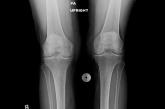

ArticleAtypical knee painAuthor:Joseph M. Schwab, MDPublish date: May 10, 2022The patient found it hard to climb stairs—and to complete a particular task when getting dressed. Difficulty with that task provided a useful diagn...Read More